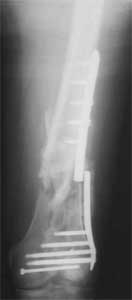

1. Percutaneous nailing is truly minimally invasive technique, but, unfortunately, nails are not reliable in many hands.

Attached are few examples from our Hospital:

A. Difficult reductions, even in retrograde nailing (my preference, easier control of "small" distal fragment) and it is much, much harder to do it anterograde (Alex, do you have one good case in your collection of anterograde nailing in very distal fractures - as you have suggested that I

should have done it in my previously posted case?

Malpositioning is much too common (recurvatum, varus - valgus).

B. Fixation loosening: distal cutting of the nail, non-unions do happen (cases attached).

Locking Plating has more distal screws than any nail, fixed angles and provides much better fixation, especially in osteoporotic bone.